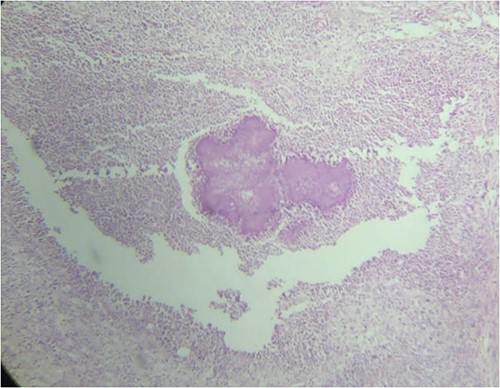

The biopsy of sigmoid colon revealed multiple nodules with abscess formation within the outer wall of bowel and focal diverticulitis. Microscopic findings showed characteristic sulfur granules of actinomycosis colony (Fig. 3). However, the culture result was negative. Intravenous antibiotic combination of 14-days ceftazidime and 5-days metronidazole was administered followed by complete resolution of symptoms.

Sulfur granules appearance revealed from histopathological examination of sigmoid colon tissue which indicate actinomycose infection.